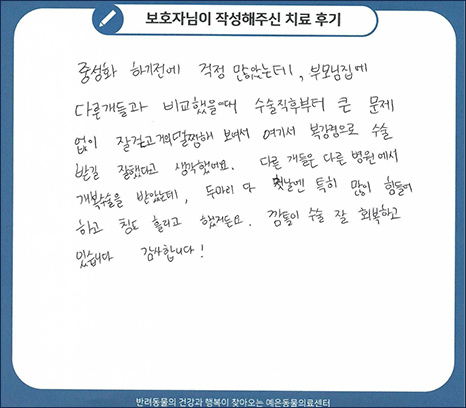

치료 후기 02

중성화 하기 전에 걱정 많았는데, 부모님집에 다른 개들과 비교했을 때 수술 직후부터 큰 문제 없이

잘 걷고 거의 멀쩡해 보여서 여기서 복강경으로 수술받길 잘했다고 생각했어요.

다른 개들은 다른 병원에서 개복수술을 받았는데, 두 마리 다 첫날엔 특히 많이 힘들어 하고

침도 흘리고 했거든요. 깜톨이 수술 잘 회복하고 있습니다. 감사합니다.